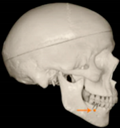

Three points determined the Acta plane: O, F right (FR), and F left (FL) (Table 2). Point O is the midpoint between the most craniodorsal point of the dorsum Sella and the most posterior dorsal point of the Basion in the midsagittal plane (Figure 1). Both points F are a result of the intersection between two lines: the line that connects the most inferior points of the lower orbital margins, right and left, and a line perpendicular to this line that runs through the most external points of the orbital margins, right and left (Figure 2). The new transverse reference plane, the Acta plane (Figure 2), is created by connecting the O-point (Figure 1) with FR and FL (Figure 2).

Figure 1.

Point O (green dot) is the midpoint between the dorsum Sella (Se) (red dot) and the Basion point (Ba) (yellow dot).